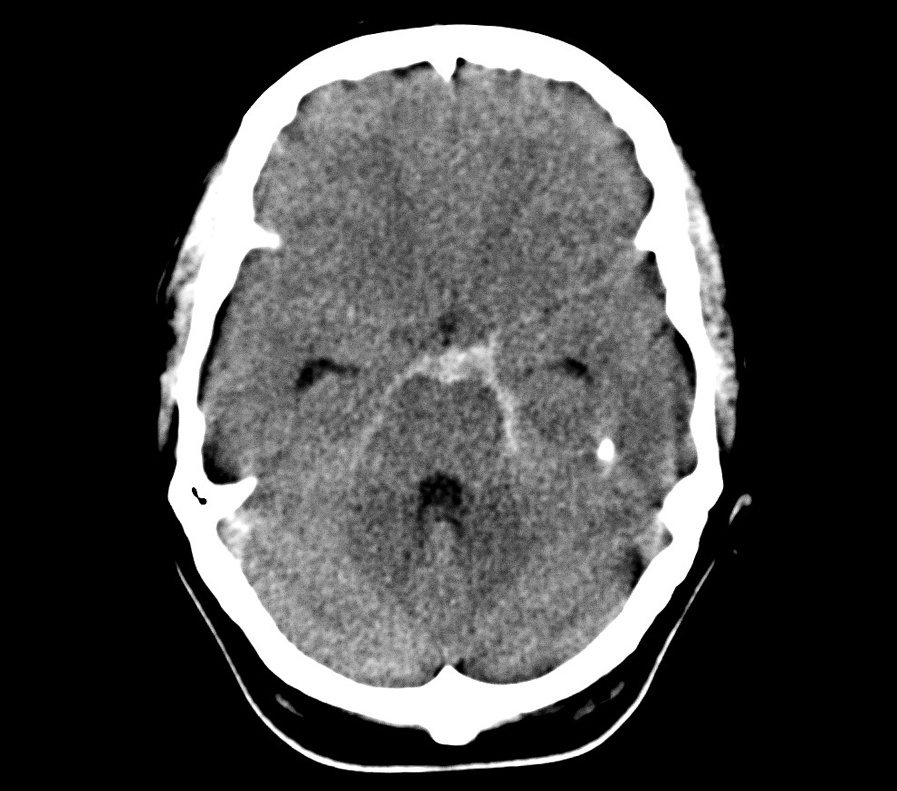

В широком смысле инсульт — это повреждение тканей мозга в результате нарушения кровообращения. По механизму воздействия его принято делить на два типа: ишемический, при котором клетки мозга недополучают крови и отмирают, и геморрагический, когда крови, наоборот, слишком много, она выходит из кровеносных сосудов и заливает часть мозга. В зависимости от места кровоизлияния геморрагический инсульт делят на внутримозговой и субарахноидальный; при последнем кровь попадает в пространство между оболочками мозга, в норме заполненное спинномозговой жидкостью.